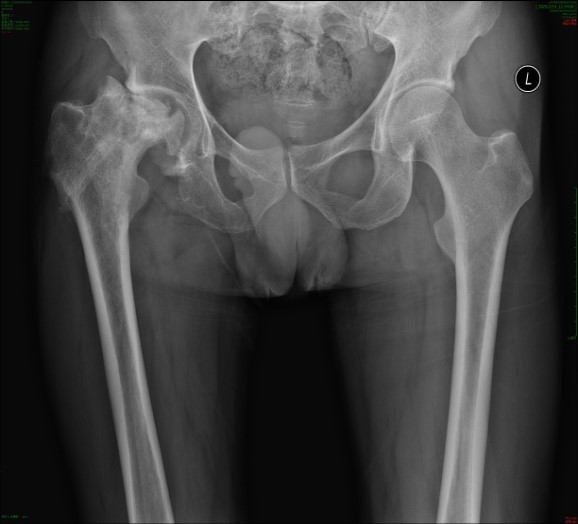

患者吕先生因高空坠落导致股骨颈骨折,进行股骨颈空心钉内固定术治疗,2年后,病情转为创伤性股骨头坏死,股骨头塌陷、变形,患肢短缩,疼痛难忍,行走困难,严重影响日常生活。传统髋关节置换手术依赖医生经验,假体植入角度和位置可能存在偏差,影响术后关节功能及远期假体使用寿命。此次手术中,陈柯主任团队利用国产“骨圣元化”关节手术机器人,通过术前精确的骨骼CT扫描,生成患者髋关节三维模型,工程师团队通过机器人系统自动规划出最佳假体型号、植入角度及深度,为吕先生量身定制了手术方案。术中,手术团队密切配合,机械臂在导航引导下精准打磨髋臼、安装假体,误差控制在0.5毫米以内,确保假体与患者骨骼完美匹配。手术过程顺利,术后病人恢复良好。